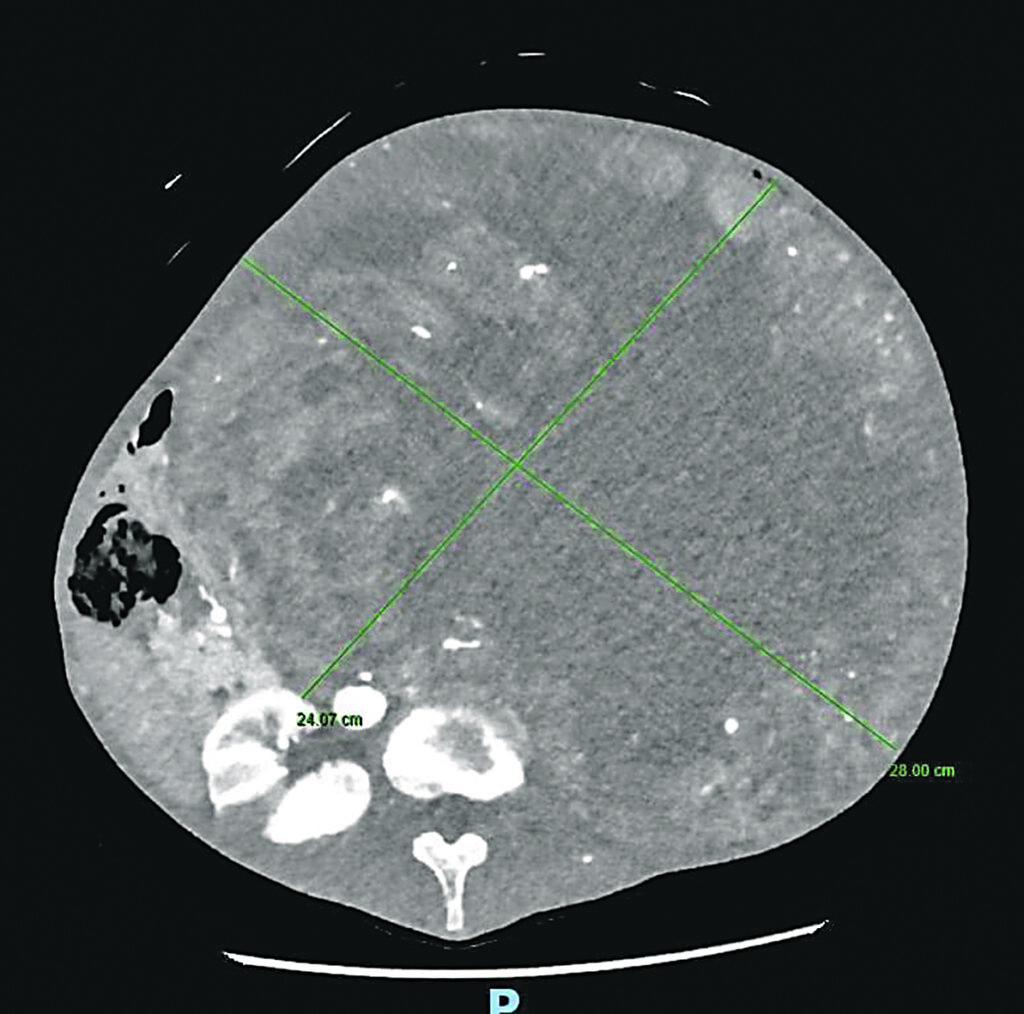

La 70enne si era rivolta al professor Guido Sciaudone, direttore della Chirurgia generale dell’ospedale di Campobasso che l’aveva visitata presso l’ambulatorio di Chirurgia colo-rettale, per un disturbo comune, la stipsi. Ma era da subito apparso evidente che il sintomo era secondario rispetto alla presenza di una voluminosa massa addominale di dimensioni spropositate che i successivi accertamenti diagnostici rivelavano essere a partenza dal rene sinistro. La massa occupava ormai l’intera cavità addominale, comprimendo oltre all’intestino tenue e al colon organi importanti quali il fegato, la milza, lo stomaco, il pancreas e il duodeno e compromettendo la circolazione sanguigna di tali strutture.

L’operazione, di estrema delicatezza e che ha richiesto estrema precisione, ha previsto diverse procedure integrate: la nefrectomia totale con l’asportazione del rene inglobato nella massa di verosimile natura etero plastica (si è in attesa dell’esame istologico definitivo), la colectomia subtotale (cioè la rimozione di gran parte del colon in quanto ischemico in seguito all’occlusione cronica ed alla sofferenza vascolare dovuta alla compressione dei vasi da parte della massa) e il confezionamento di una derivazione intestinale esterna per permettere la canalizzazione.